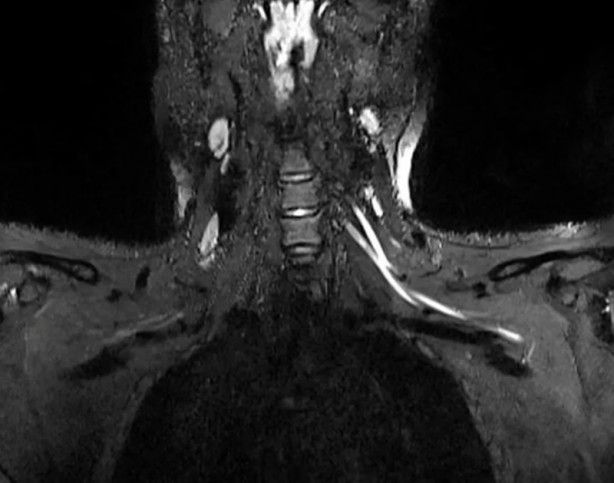

Radiology dergisinde yayımlanan çalışmanın başyazarı Doktorlar Ağrı boynunuzdaki, dirseğinizdeki veya bileğinizdeki sorunlardan kaynaklanıyor olabilir ve bunu anlamanın en iyi yolu MRI veya ultrasondur. Yaptığımız çalışmayla çok küçük sinirleri bile gösteren gelişmiş görüntüleme sunuyoruz. Bu da sorunun nerede olduğunu tespit etmemize, ciddiyetini değerlendirmemize ve buna neyin neden olabileceğini önermemize yardımcı olabilir.

Öte yandan, çalışmanın yazarları gelişmiş ultrason teknolojisinin kolay taşınabilir ve ucuz olduğunu, ayrıca sinir hasarını tespit etmede tomografiden daha iyi olduğunu ifade etti. Araştırmacılar, taramaların doktorların hastaları bir rehabilitasyon uzmanına mı yoksa daha ciddi durumlarda bir cerraha mı sevk edeceklerine dair karar vermelerine yardımcı olacağını aktararak, “Eğer görüntüleme enflamatuar bir tepkiye bağlı sinir hasarı bulursa, hastaya bir nöroloğa görünerek daha iyi hizmet edilebilir. Görüntüleme, hematomdan kaynaklanan sinir hasarını ortaya çıkarırsa, kan sulandırıcı ilaçların derhal ayarlanması gerekir ve hatta hastanın bir cerrahı görmesi gerekebilir” açıklamasını yaptı.